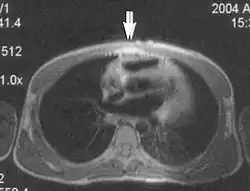

Flow

Flow can manifest as either an altered intravascular signal (flow enhancement or flow-related signal loss), or as flow-related artifacts (ghost images or spatial misregistration). Flow enhancement, also known as inflow effect, is caused by fully magnetised protons entering the imaged slice while the stationary protons have not fully regained their magnetization.[1] The fully magnetized protons yield a high signal in comparison with the rest of the surroundings. High velocity flow causes the protons entering the image to be removed from it by the time the 180-degree pulse is administered. The effect is that these protons do not contribute to the echo and are registered as a signal void or flow-related signal loss (Fig. 2).[1] Spatial misregistration manifests as displacement of an intravascular signal owing to position encoding of a voxel in the phase direction preceding frequency encoding by time TE/2.The intensity of the artifact is dependent on the signal intensity from the vessel, and is less apparent with increased TE.[1]